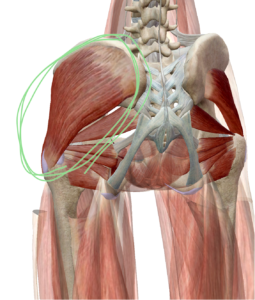

本日お尻の筋肉の“中臀筋”という筋肉についてお話ししていきたいと思います。

中臀筋は骨盤を安定させてり股関節の安定などにか風ない筋肉です。

↑↑↑

この◯の部分が中臀筋になります。

骨盤と股関節をつないでいるのがわかると思います。

この中臀筋が正常に働かなくなると腰痛になります。

中臀筋は主に歩行時などに骨盤を安定させたり、足を出す時や踏み込んだ時に働きます。

中臀筋由来の腰痛持ちの方は非常に多いです。